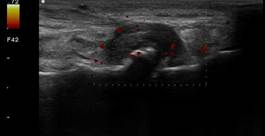

Problemen met een breukje in een bot

Een klein breukje (stressfractuur of scheurtje) in een bot kan flinke pijn veroorzaken, ook als het op een gewone röntgenfoto nog niet goed zichtbaar is. Met echografie kunnen wij veranderingen rond het bot beoordelen, zoals zwelling, vocht of een onderbreking in het botoppervlak. Zo krijgen we snel duidelijkheid over de plek en ernst van het letsel en kunnen we uitleg geven over passende vervolgstappen.